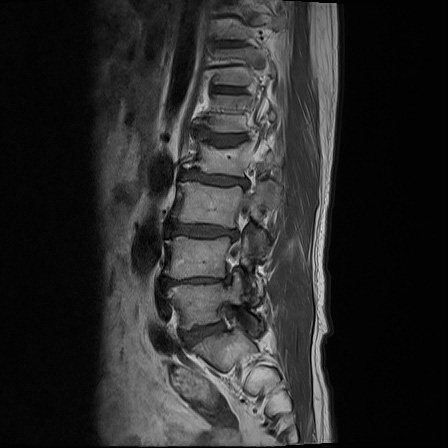

Ӵϲ ɿ ô ô 㸮 ٸ ̾ϴ. ϵ Ͻð ܻ 㸮 20⵿ ͽϴ. mri ˻ ɿ Ȳ ʹ ؼ Ȳ̶ ߽ϴ. ϻȰ ϰ 鼭 ½ϴ. ̴ ø鼭 Ͻô Ȳ ̷ ġ ص ȸ ϴ. δ Ҵµ, ù ȸԲ ˷ֽ ϰ β ϰ, ˷ֽ ü ƮĪ ϸ鼭 ȭǸ鼭 Ӵϲ ȸų ְ ǰ, β 鼭 ʴ β ؾϴ ŷο 1ϸ ijħ ڸ ǥ Ʈ ߽ϴ. ȸ ȭϽø鼭 Ϸ簡 ٸ ȸǽð 4ְ Ǿ Ǯ鼭 ¦ ҽϴ. ħ ȸ ȭϸ鼭 ڼ ü ƮĪ ϴ. ȥڼ Ͻʴϴ. ٳø鼭 ó Ͻ ʴϴ. ̾ ְ ̳ ߵ ʰ ϴ ȸԲ Ͻʴϴ. ʹ ϸ鼭 ϴ. Ȩ - ϱ ٴ Ȳ MRIԴϴ. |